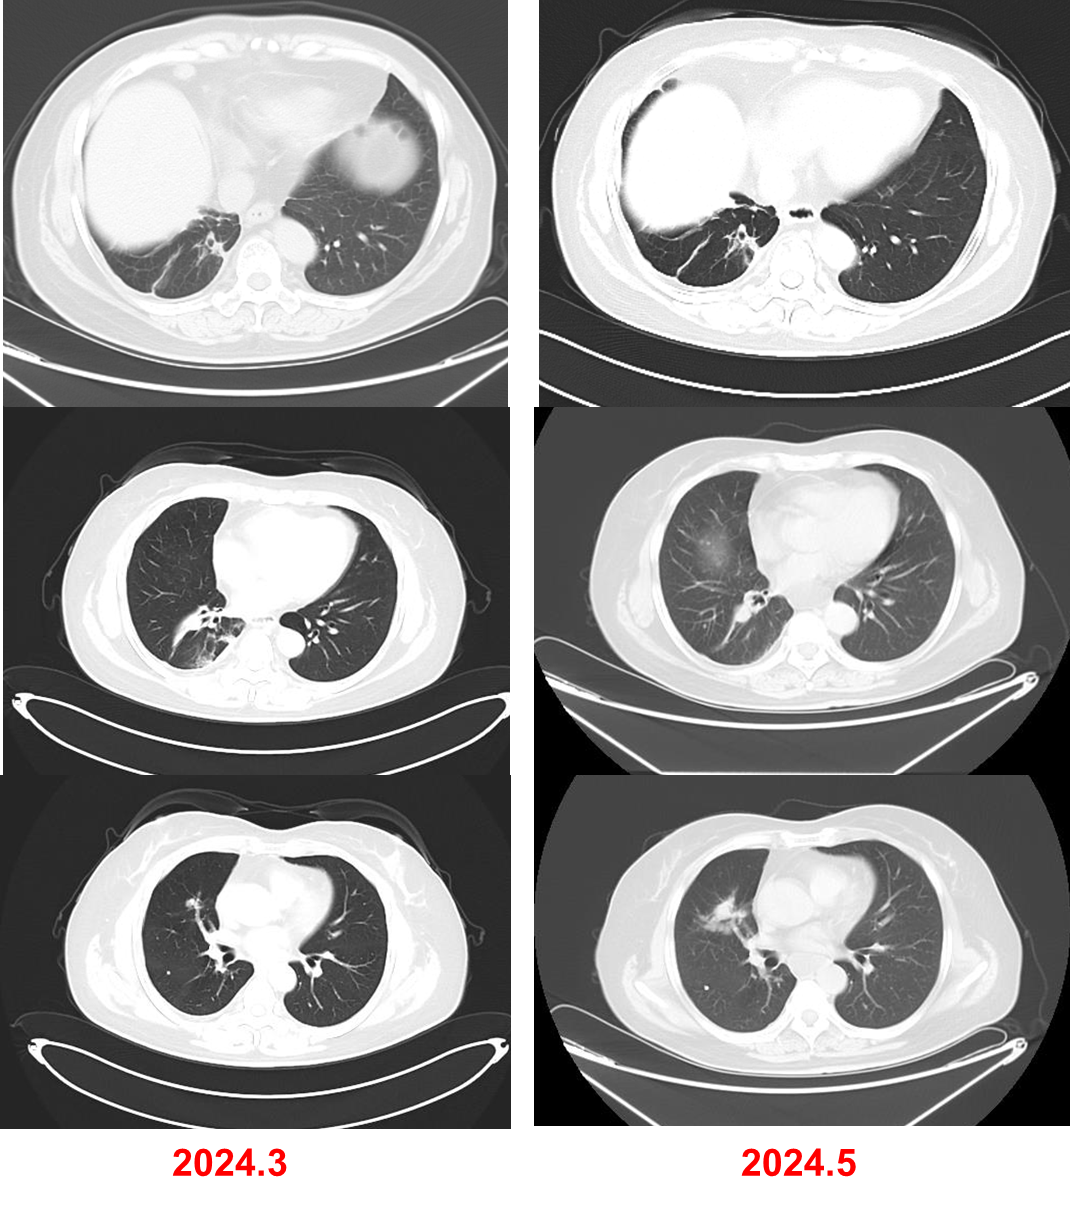

2023年2月,查胸部增强CT(图1)示:右肺下叶病变,伴部分肺实变,右侧肺门及纵膈内多发增大淋巴结,双肺多发磨玻璃结节。全身骨ECT(2022-03-03,图2)示:左6前肋骨代谢增高;T5、L5椎体骨代谢增高,结合病史提示骨转移。腹部CT、头颅MRI未见明显转移。

2024年5月,复查CT,评估为SD,但病灶略有增大。